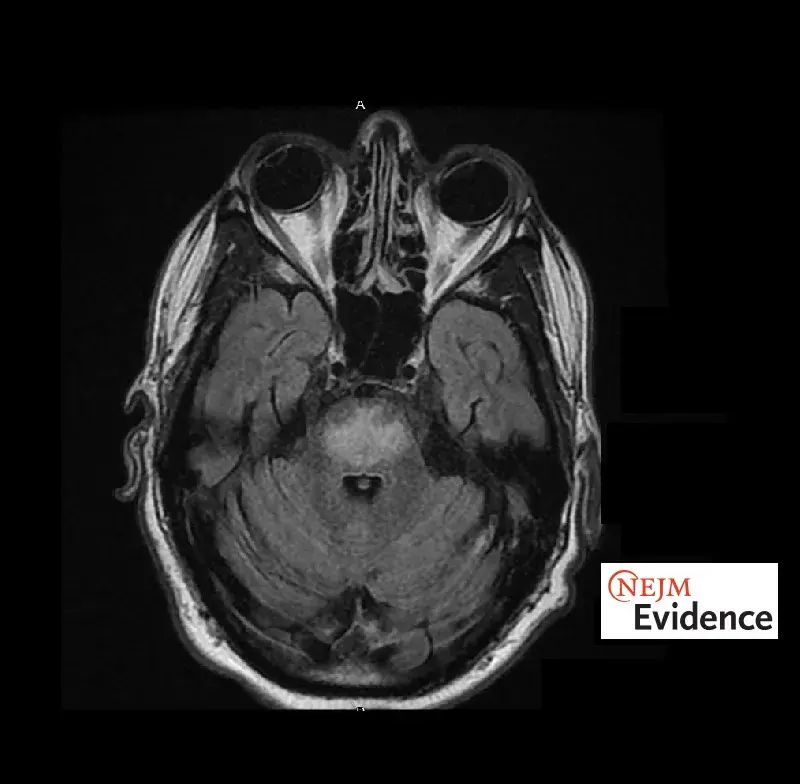

Síndrome da Desmielinização Osmótica: Rara, mas potencialmente grave!